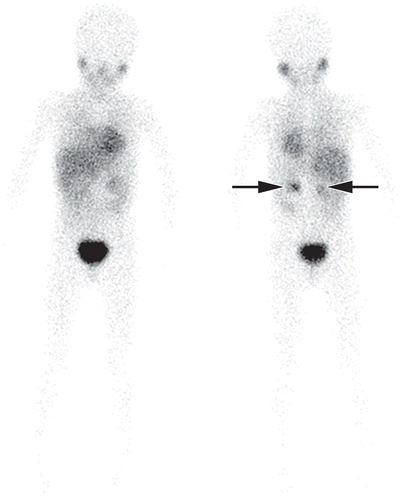

A Pesquisa de Corpo Inteiro com MIBG 123I é um exame de imagem nuclear que utiliza um traçador radioativo específico para avaliar a presença e a localização de tumores neuroendócrinos, como o feocromocitoma e o neuroblastoma, além de outras condições médicas. Este exame é fundamental para o diagnóstico, estadiamento e acompanhamento de várias doenças.

A Pesquisa de Corpo Inteiro com MIBG (Metaiodobenzilguanidina) 123I é uma forma de cintilografia que utiliza o isótopo radioativo Iodo-123, associado ao MIBG. O MIBG é um composto que se liga a células tumorais e neuroendócrinas, permitindo que sejam visualizadas com precisão por meio de imagens obtidas com uma câmara gama.

- Feocromocitoma e Neuroblastoma: Identifica e localiza tumores neuroendócrinos, como feocromocitomas (tumores da glândula adrenal) e neuroblastomas (tumores do sistema nervoso simpático), que podem ser difíceis de detectar com outros métodos de imagem.

- Avaliação da Extensão da Doença: Determina a extensão e a localização de tumores neuroendócrinos no corpo, ajudando a planejar o tratamento e a avaliar o prognóstico.

- Captura das Imagens: O paciente é posicionado sob uma câmara gama que detecta a radiação emitida pelo MIBG 123I. São obtidas imagens do corpo inteiro para identificar a distribuição do traçador.

- Análise dos Resultados: As imagens obtidas são analisadas por um radiologista especializado, que avalia a presença e a localização de tumores ou outras anomalias.

A Pesquisa de Corpo Inteiro com MIBG 123I é uma ferramenta essencial para o diagnóstico e o gerenciamento de tumores neuroendócrinos. Sua capacidade de fornecer imagens detalhadas da distribuição do traçador permite uma avaliação precisa da extensão da doença e da resposta ao tratamento.